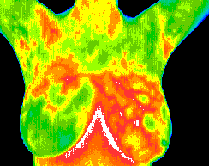

This non-invasive, pain-free, and radiation-free screening tool captures the heat patterns on the skin’s surface, providing valuable insights into various health conditions.

Thermography works by capturing the heat patterns on the skin's surface. These heat patterns can reveal abnormalities and dysfunctions in the body. The procedure is simple and involves no direct contact with the body.

A thermographic camera is used to take images of different body parts, which are then analyzed for heat patterns that may indicate potential health issues.

Thermography images are reviewed by board-certified medical doctors trained in thermology.